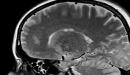

هو فقدان الوعي بشكل مؤقّت ثمّ العودة إلى الوعي بشكلٍ كاملٍ بسبب انخفاض تدفّق الدم إلى المخ، وانخفاض معدل ضربات القلب، ويطلق عليه أيضاً مصطلح (الغشي)، وتكون هذه الحالة مصحوبة بسقوط الشخص في حال وقوفه، أو جلوسه بسبب فقدان السيطرة على عضلات الجسم لفترة قصيرة لا تتعدّى بضع دقائق، والإغماء يحدث في بعض الأحيان دون سابق إنذار، وفي أحيان أخرى يسبقه العديد من العوامل التي تشير إلى إمكانيّة حدوث حالة الإغماء كالدوخة، والغثيان، والتقيؤ، والحمى، وغيرها من العوامل التي تنذر بإمكانية حدوث الإغماء.

- أمراض الأوعية الدمويّة في المخّ، كالصداع النصفي، وقصور الفقري القاعدي.

- بطء نبض القلب، والذي يؤثّر على قدرة الجسم على الحفاظ على ضغط الدم بشكل سليم، وتدفّقه إلى المخّ بكميّة كافية.